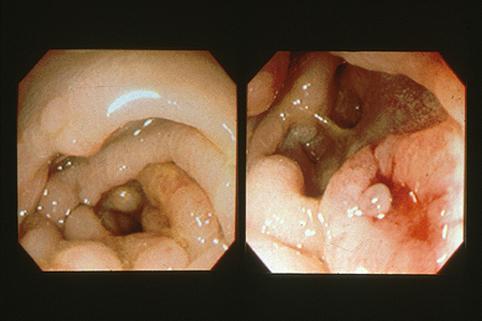

疾患(病理主体)の分類悪性上皮性腫瘍/腺癌

部位(臓器別)大腸/S状

検査方法内視鏡

腫瘍の肉眼分類3型(潰瘍浸潤型)/

病変の最大径(ミリ)40以上

腫瘍の深達度s(a)